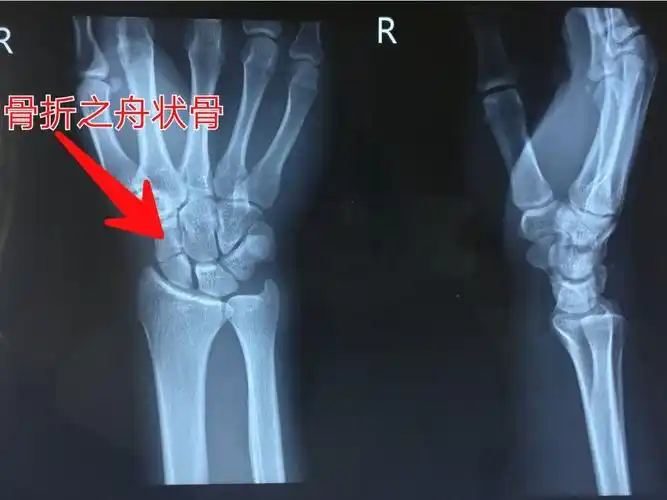

左手手腕舟骨骨折,这受伤程度严重吗?目前已夹板固定敷药8天.

手腕舟骨骨折经历

腕舟骨骨折

避免腕舟骨骨折并发症一定注意这几点